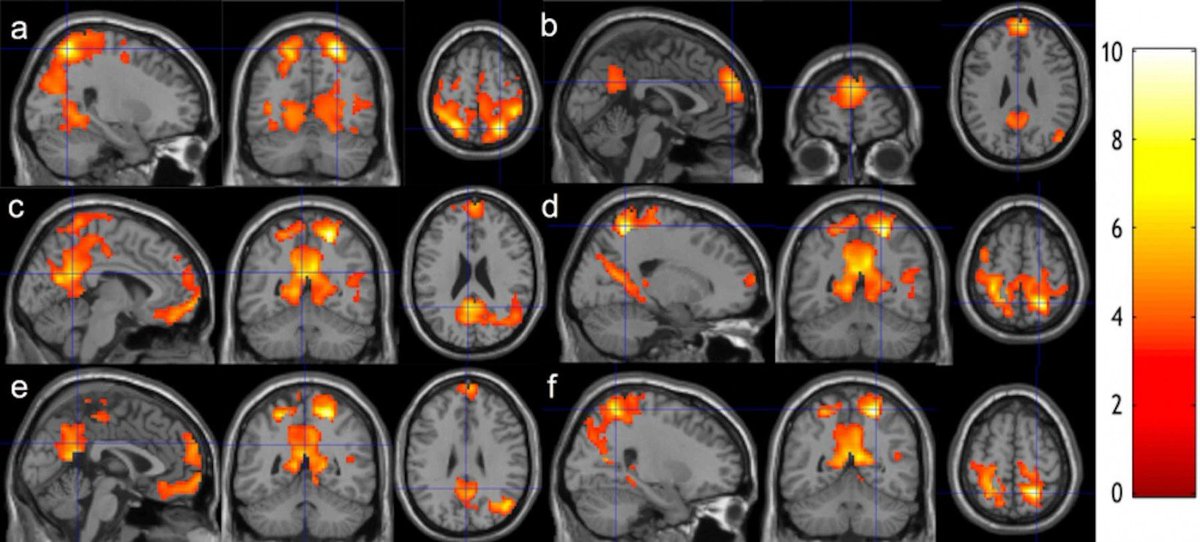

It's rewiring your brain.

Harvard studies show it rebuilds your brain’s gray matter in 8 weeks.

Imagine 6 months!

You’re not just relaxed; you're reborn. Image